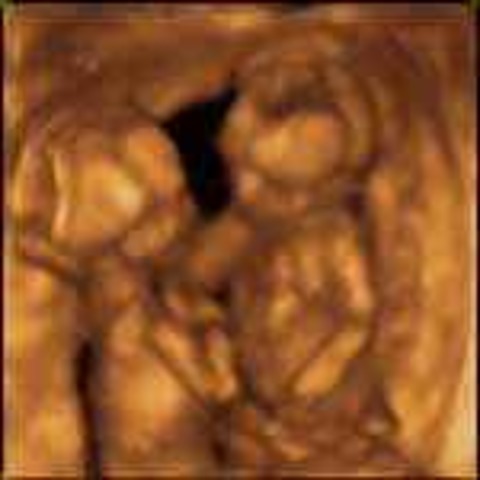

• Week 13: Baby Flexes and Kicks

Week 13: Baby Flexes and Kicks

Fetus has grown to about 3 inches long, weight is 1 ounce, bone is beginning to replace cartilage, ribs are appearing, nose and chin are well defined, movements can be measured, child can open/close mouth, external genitalia are almost defined- may be possible to tell gender